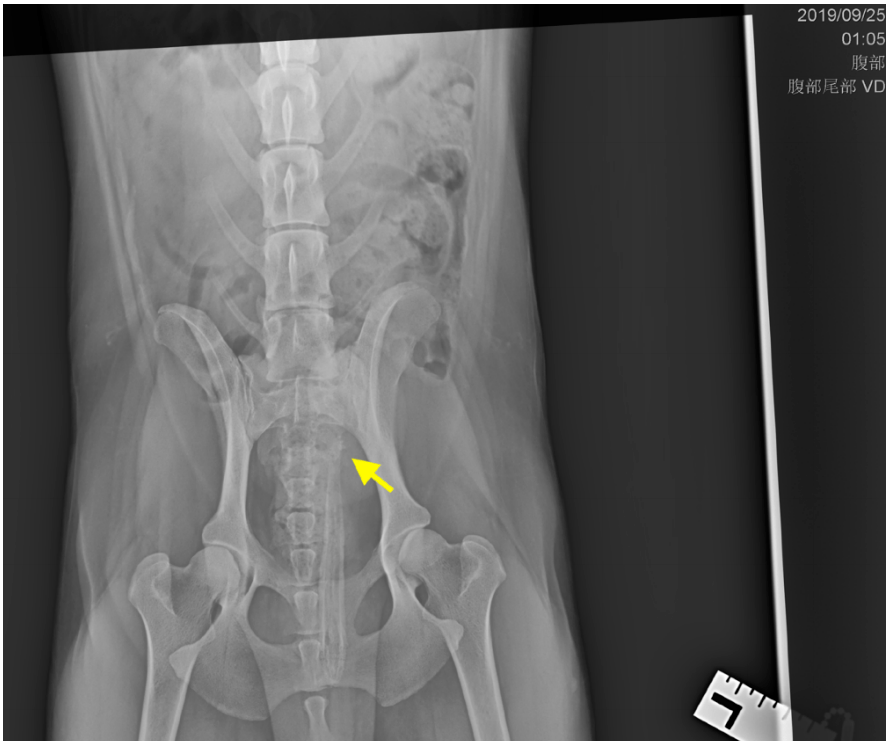

数字化x光线(dr)拍出膀胱及尿道有结石

图4:腹部右侧卧x光片,膀胱轻度充盈,黄色箭头处,可见多个细碎不透射